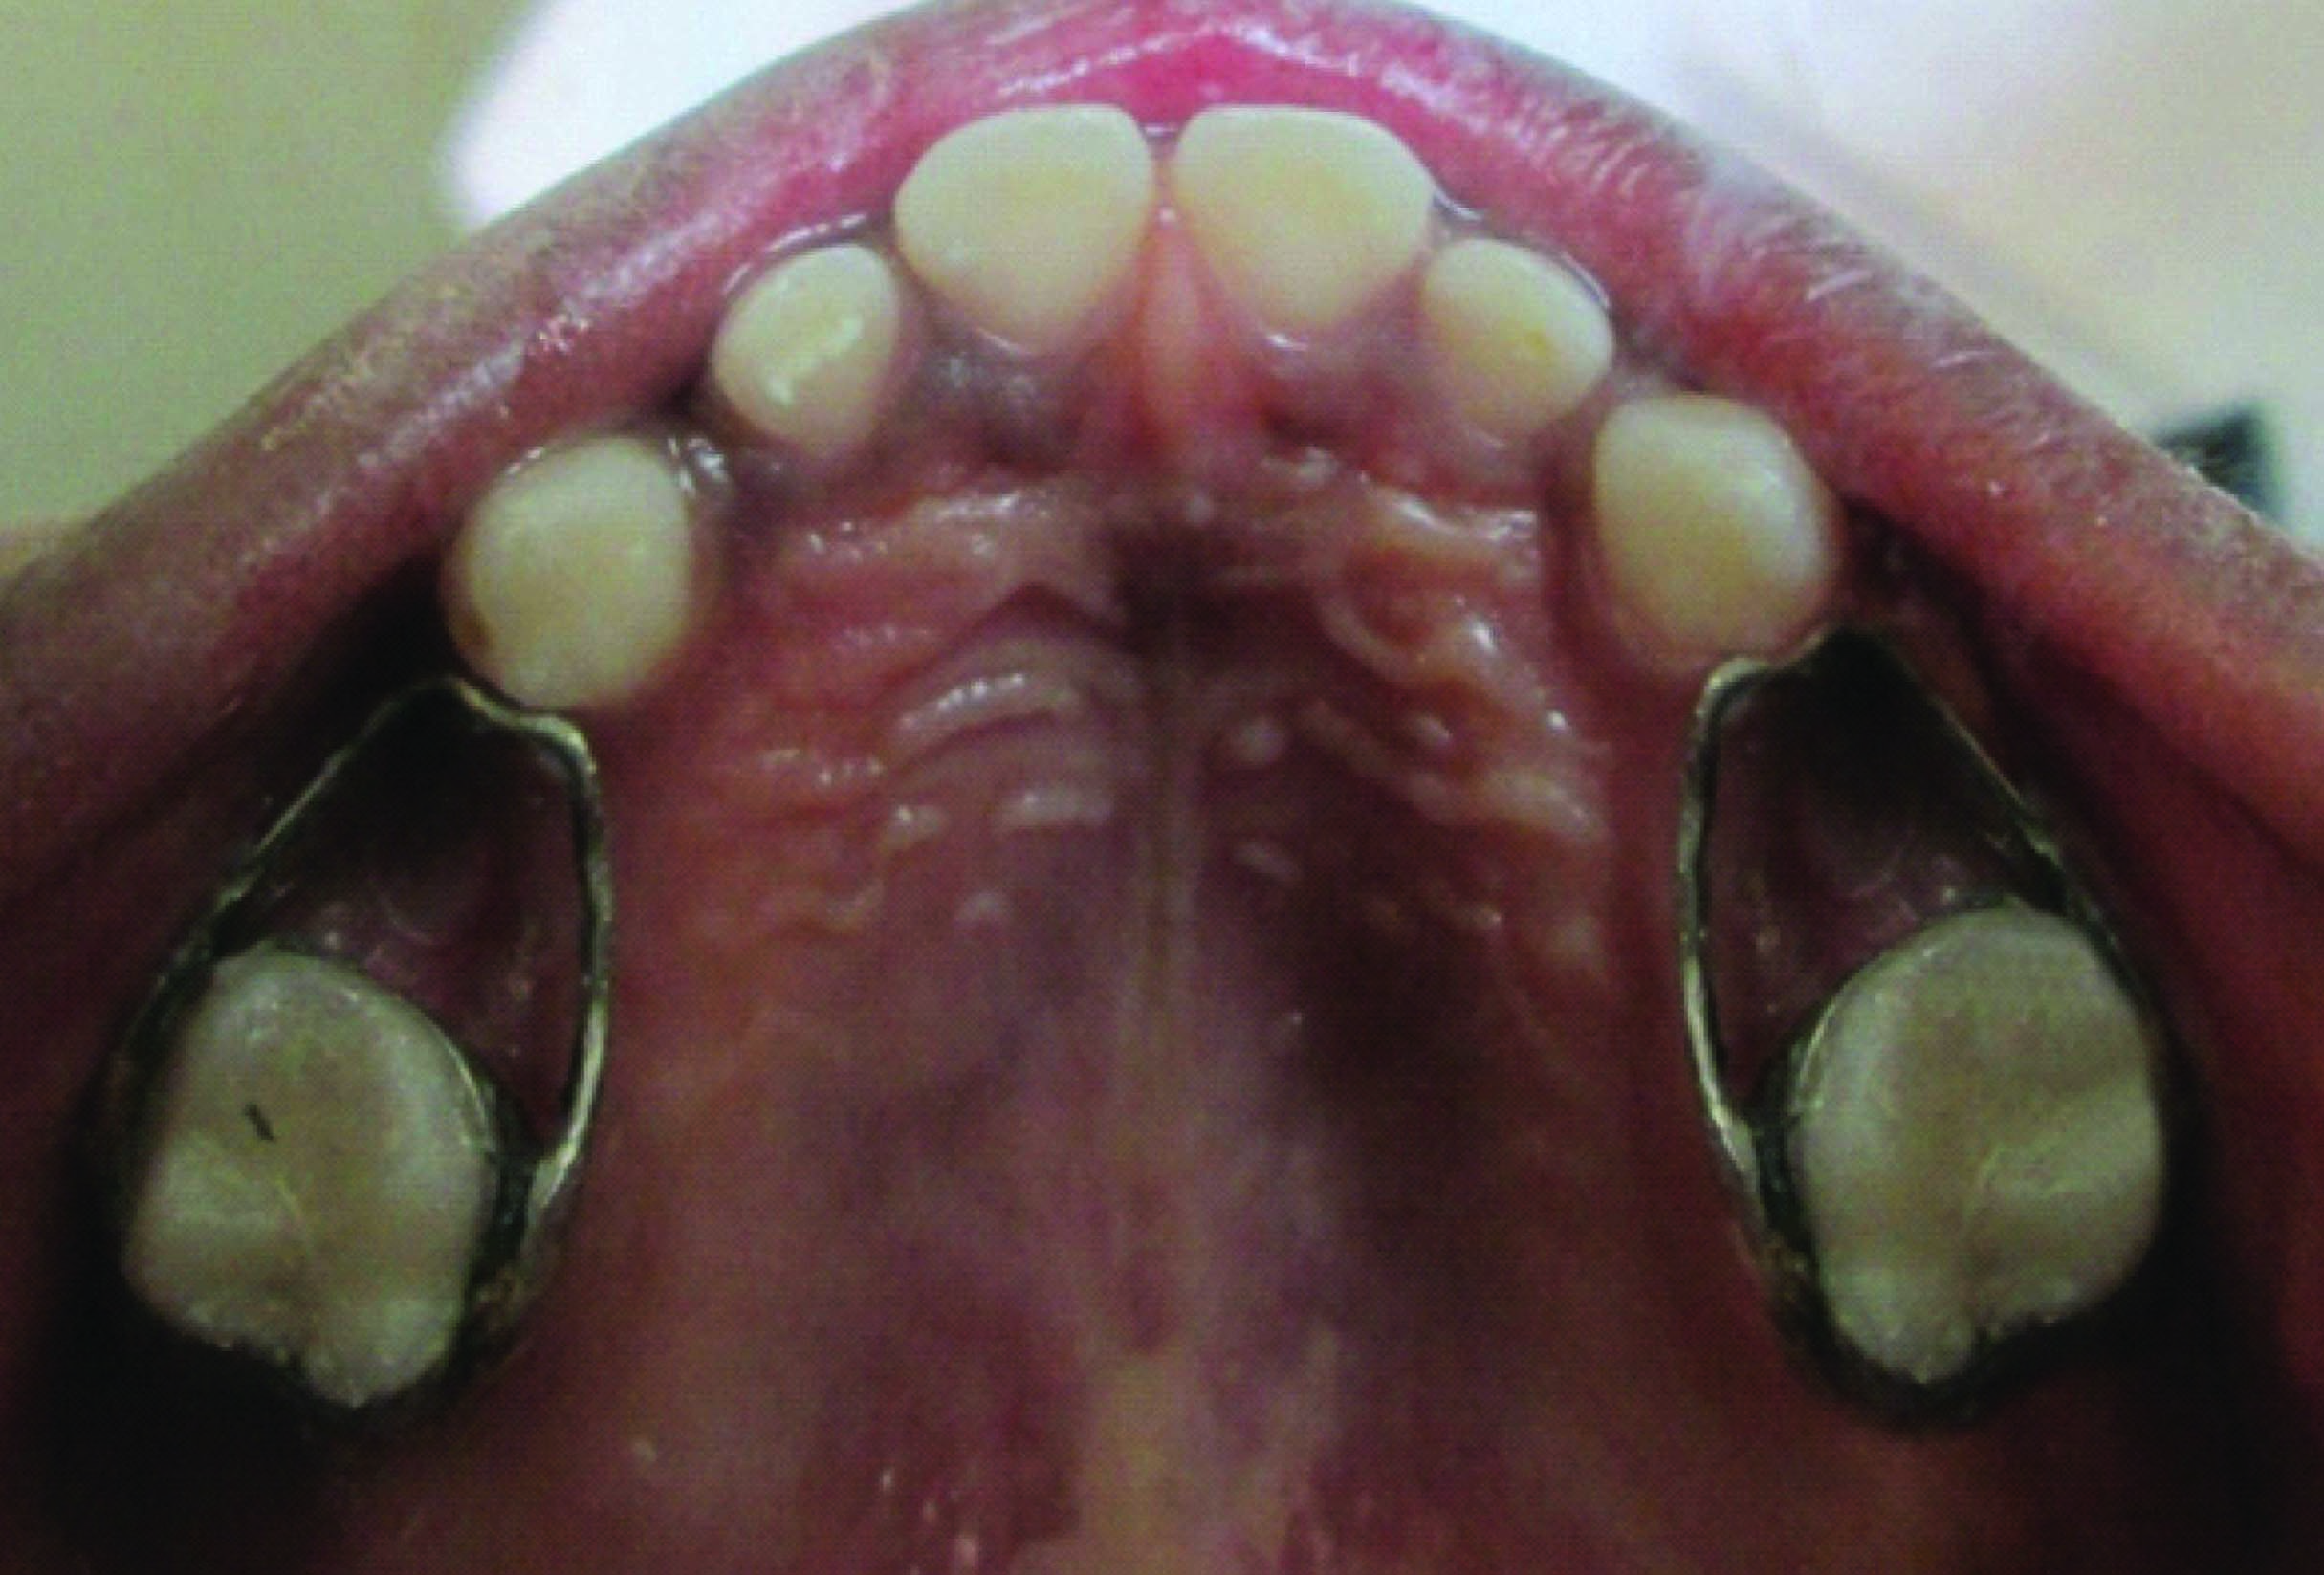

Extraction followed by space maintainer was planned for 64 and 85 [Table/Fig-4, 5]. On further examination of the patient’s sibling’s similar characteristic radiographic finding of taurodontism was discovered. IOPA of 84, 85 region of brother [Table/Fig-6] and IOPA of 84 region [Table/Fig-7] of sister exhibited taurodontic characteristic. Suspecting this the mother was also subjected to radiographic procedure who to our great surprise exhibited taurodontic appearance of a previously endodontically treated 36 [Table/Fig-8].

Intraoral picture showing band and loop space maintainer in 55 and 65